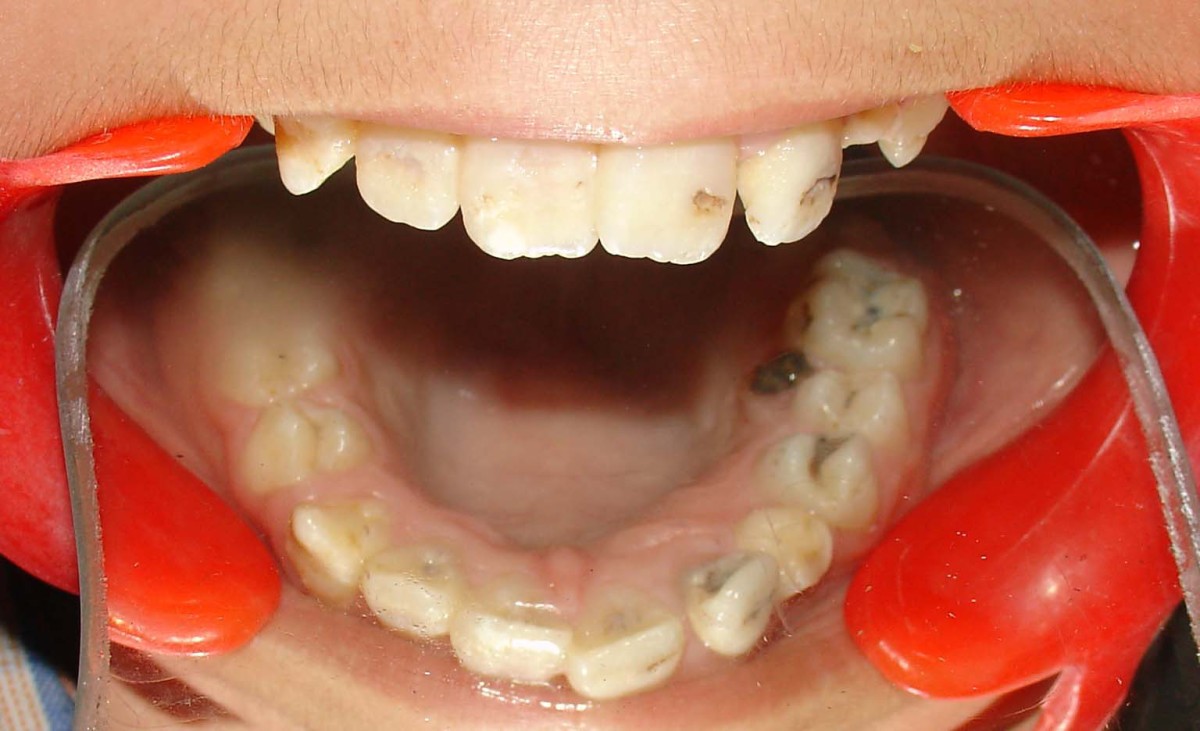

From pubs.sciepub.com

Figure 1. Intraoral photograph of the patient Dentin Dysplasia Type I What Is Dentin Dysplasia dentin dysplasia is a rare genetic condition that can cause the tissue to form in abnormal ways, and it can have. dentin dysplasia (dd) is a rare disorder belonging to the group of hereditary dentin defects and is characterized by abnormal. learn about dentin dysplasia type ii, including symptoms, causes, and treatments. dentin dysplasia (dd) is. What Is Dentin Dysplasia.